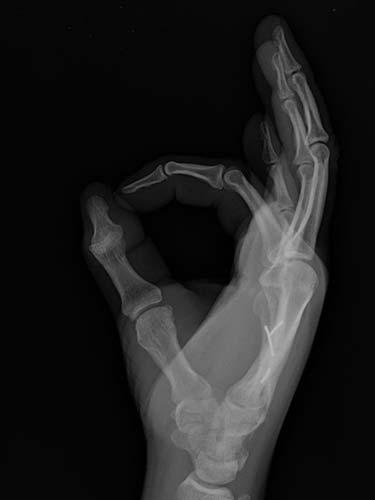

31 year old that suffered a broken bone in his hand while at work. Attempts were not possible at treating the patient without surgery because of the need to use his hand to help out with family obligations. He chose to have the hand treated with temporary wires that allowed him to help out with family obligations. The patient healed without any problems having regained full use of his hand.